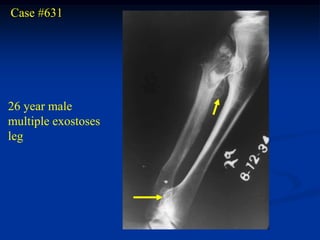

Case #631

26 year male

multiple exostoses

leg